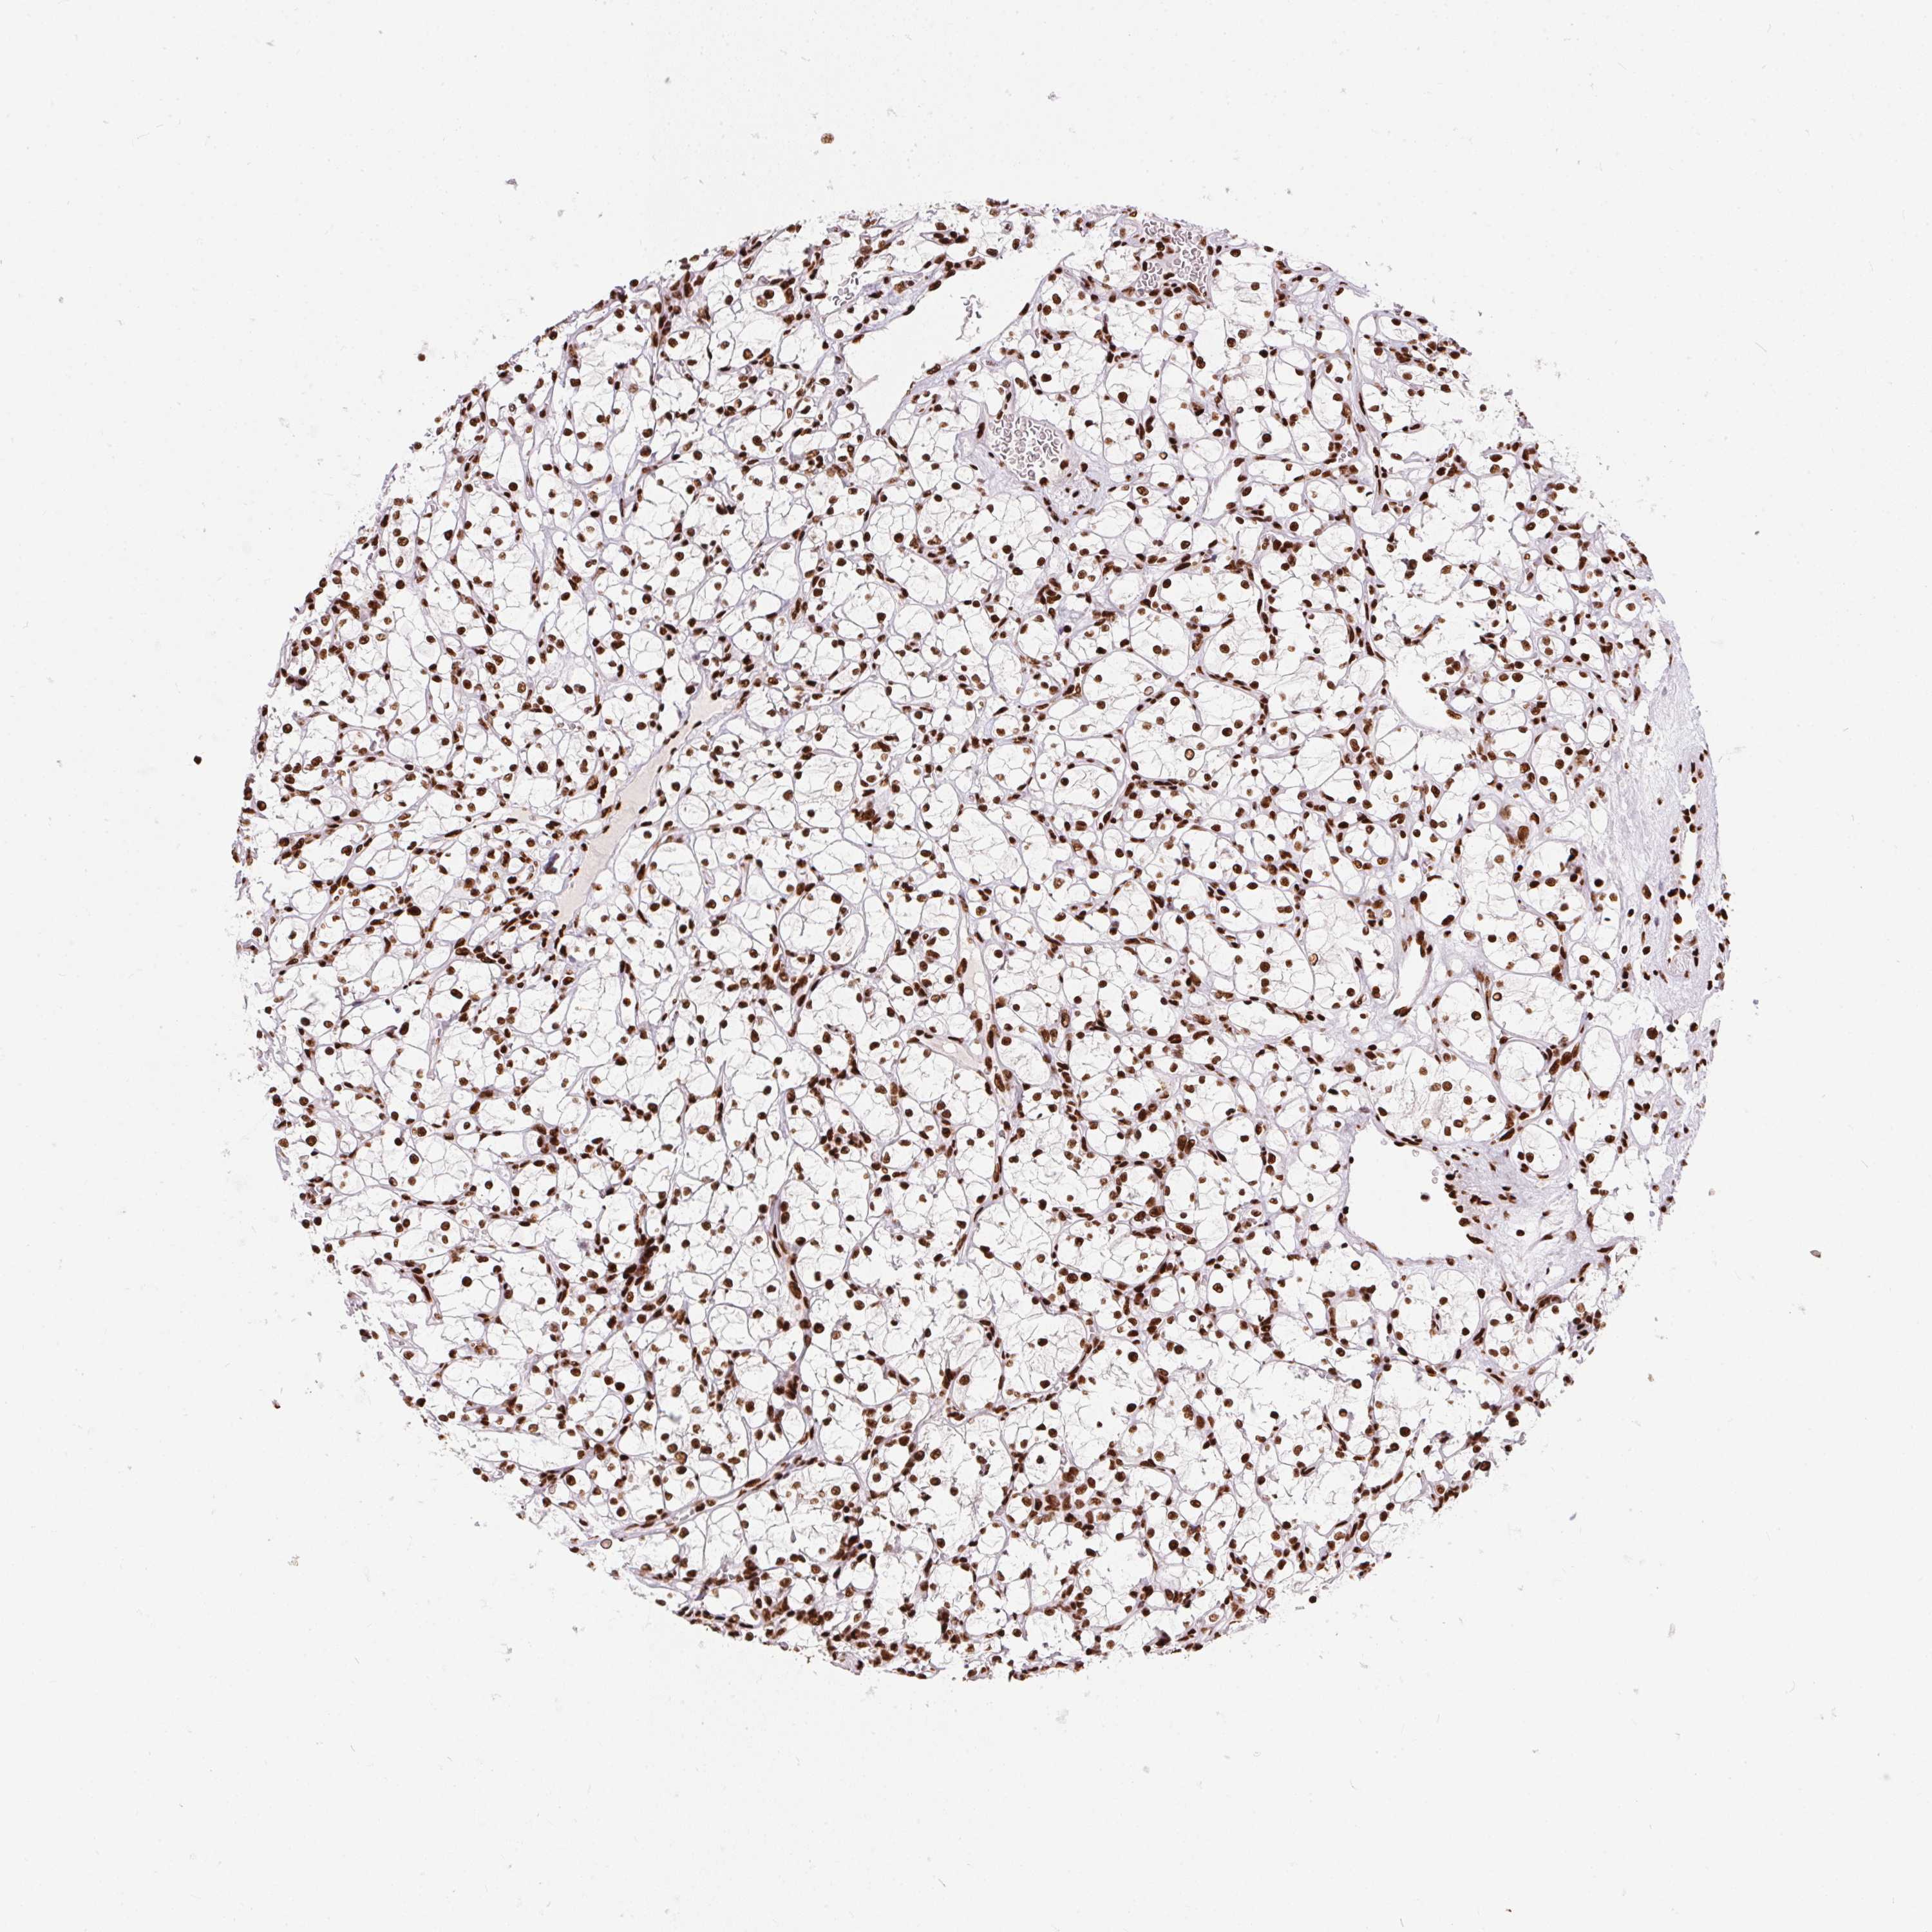

TCGA RNA samplesi

RNA-seq data is reported as average FPKM (number Fragments Per Kilobase of exon per Million reads), generated by the The Cancer Genome Atlas (TCGA) .

Normal distribution across the dataset is visualized with box plots, shown as median and 25th and 75th percentiles. Points are displayed as outliers if they are above or below 1.5 times the interquartile range. FPKM values of the individual samples are presented next to the box plot.

Average pTPM 0.0

Number of samples 100